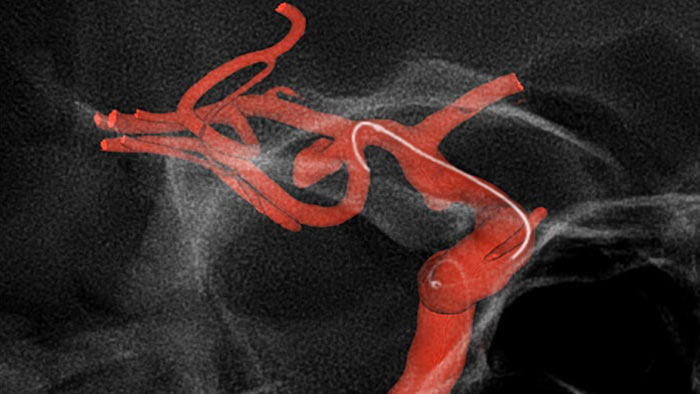

Roadmap Pro

SmartCT Roadmap

Enhance visualization of overlapping vessels to support precise navigation of guidewire and catheter through complex vasculature. Offers high-level precision with real-time compensation for gantry, table and small patient movements. Customize Roadmap Pro to show advancement during coil placement.